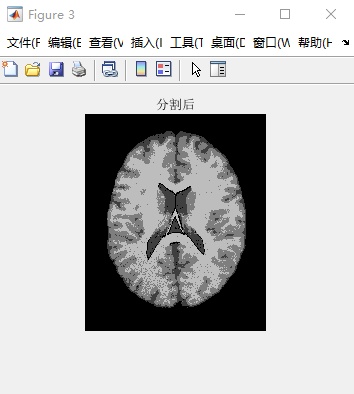

完成对T1模态和ICMB协议下的图像处理任务,并设定切片厚度为1毫米、噪声水平达到7%以及灰度不均匀程度控制在40%后完成第90层脑部断层图像的分割处理。由于FCM算法依赖于随机初始值的选取,在实际应用中容易导致聚类结果出现偏差,并且这些偏差会对最终的分类效果产生较大的影响。